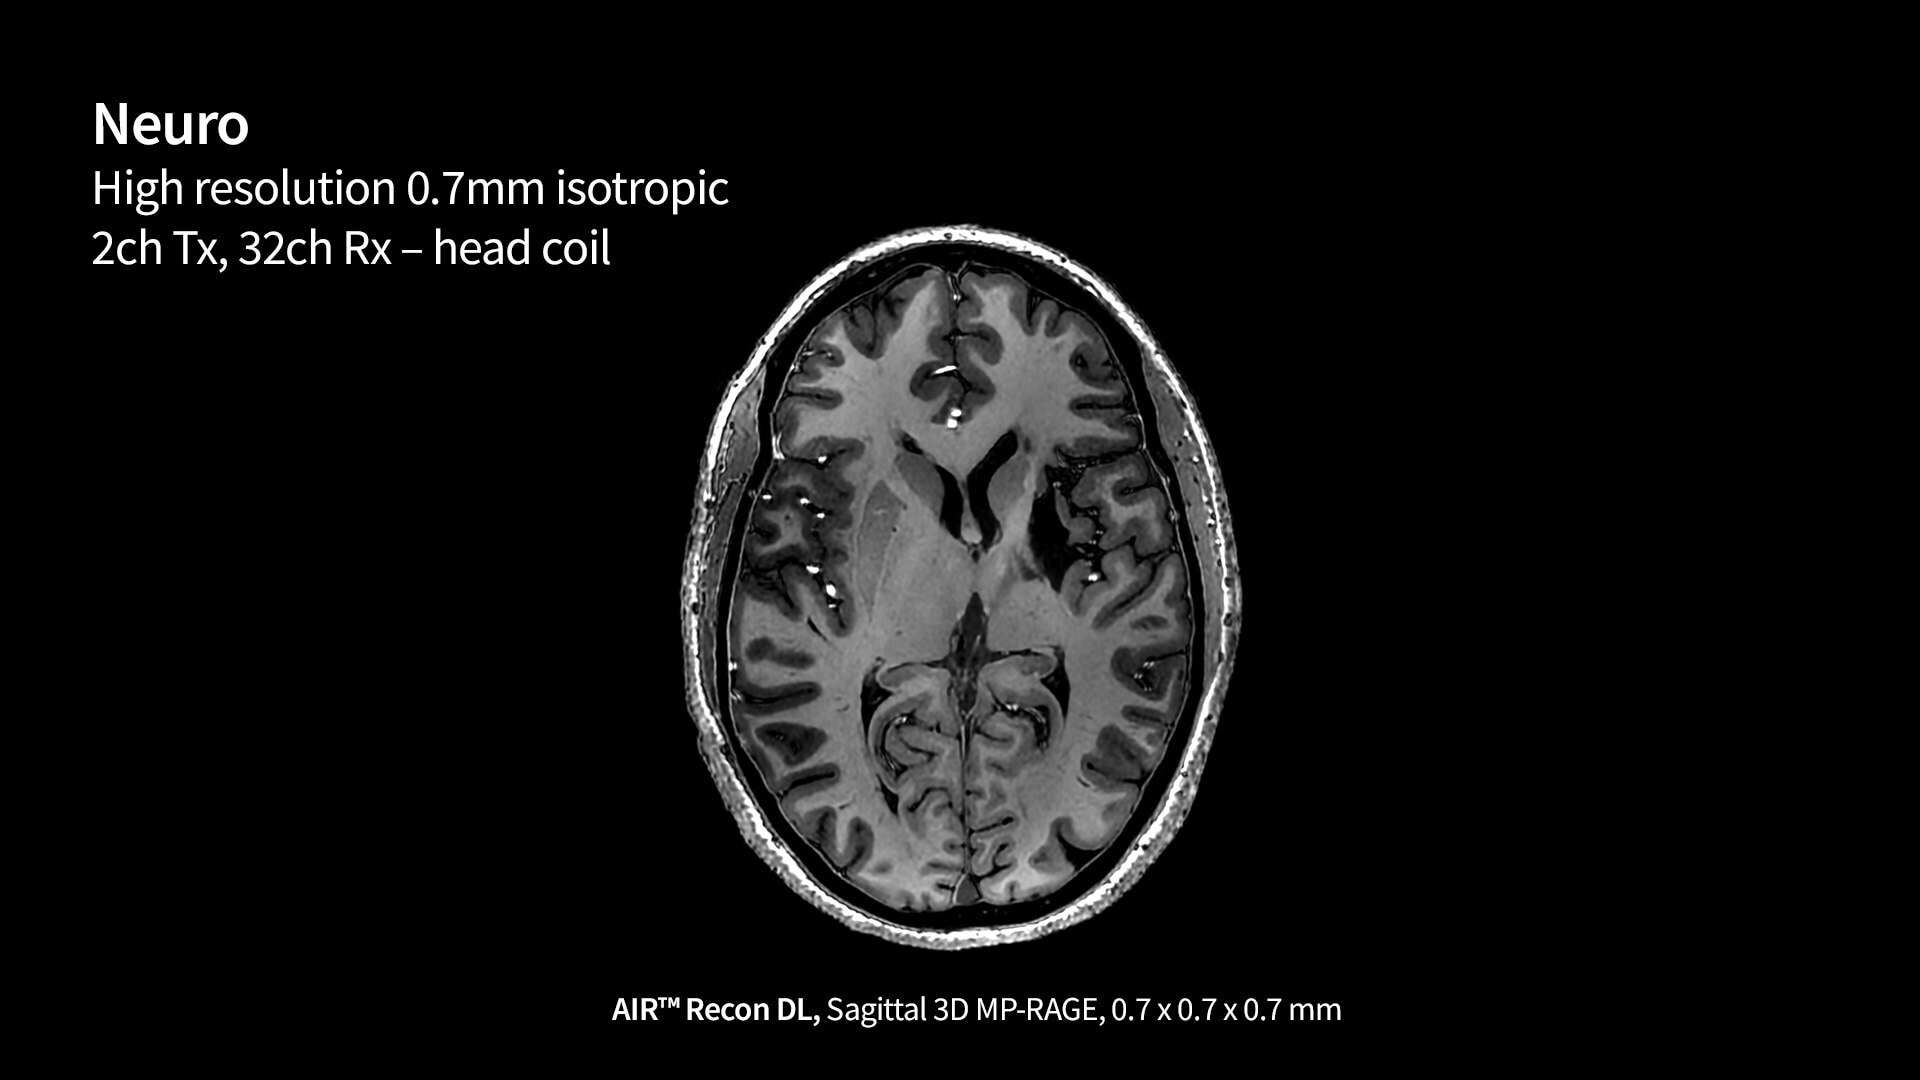

Designed to overcome the limitations for many of today’s clinical MR systems, the SIGNA™ 7T is a powerful new platform for advancing neurological research and clinical translation. Approximately five times more powerful than most clinical systems, SIGNA™ 7T is designed to detect subtle structures that may be significant for clinicians and researchers alike. Boost advanced applications with GE HealthCare's most powerful whole-body gradient platform to date, delivering exceptional resolution and contrast-to-noise ratio.

SIGNA 7T powered by a common suite of SIGNA Imaging Applications

Users have access to our latest state-of-the-art applications along with deep-learning tools like AIR x™ Brain and Knee as well as AIR™ Recon DL, while delivering the diagnostic confidence of an ultra-high-field system.